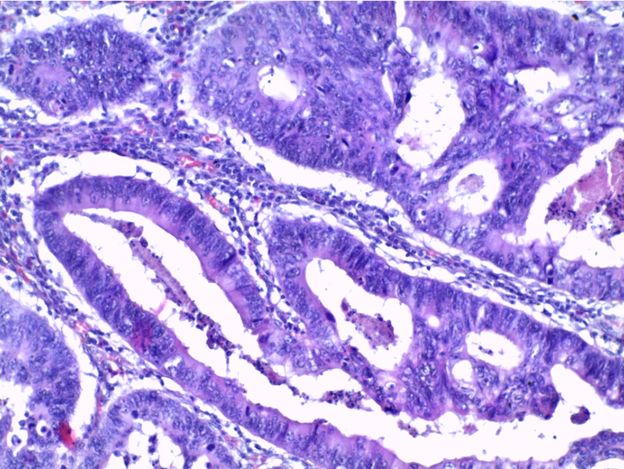

Препарат № 381

АДЕНОКАРЦИНОМА В ВОРСИНЧАТОЙ АДЕНОМЕ ТОЛСТОЙ КИШКИ

Окраска: гематоксилин-эозин

Полиповидное опухолевое образование толстого кишечника из пролиферирующего железистого эпителия с признаками дисплазии, покрывающего ворсинчатые выросты – аденома. В опухоли определяются очаги инвазивной внутрислизистой аденокарциномы в виде плохо сформированных сливающихся железистых комплексов из атипичного эпителия. В крае препарата сохранена нормальная слизистая толстой кишки.

Отметить:

1. Ворсинчатая аденома

2. Аденокарцинома

3. Нормальная слизистая.